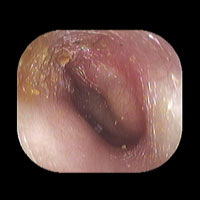

右急性中耳炎(中等症)

鼓膜がやや赤くなっています。鼓膜の奥に膿が透けて見えています。鼓膜の腫れはありません。抗生剤の内服で鼓膜切開を行わずに16日目で治りました。

初診日